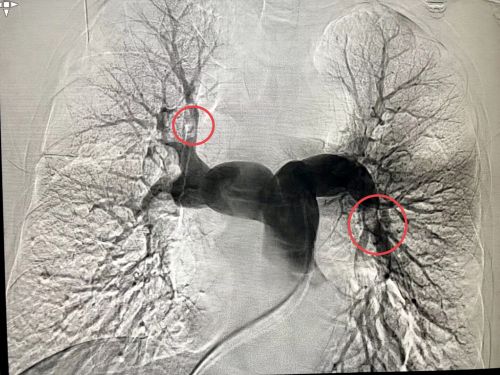

肺动脉造影结果显示肺栓塞(红圈内)。

潘宏伟主任医师等为患者进行急诊冠状动脉造影和肺动脉造影。

听了家属的描述后,潘宏伟高度怀疑老人是因为打麻将久坐不动,造成血流缓慢,血液变得粘稠,因此产生下肢静脉血栓,继发肺动脉栓塞,当即为他加做了肺动脉造影,果不其然,造影结果提示:多处肺动脉栓塞!